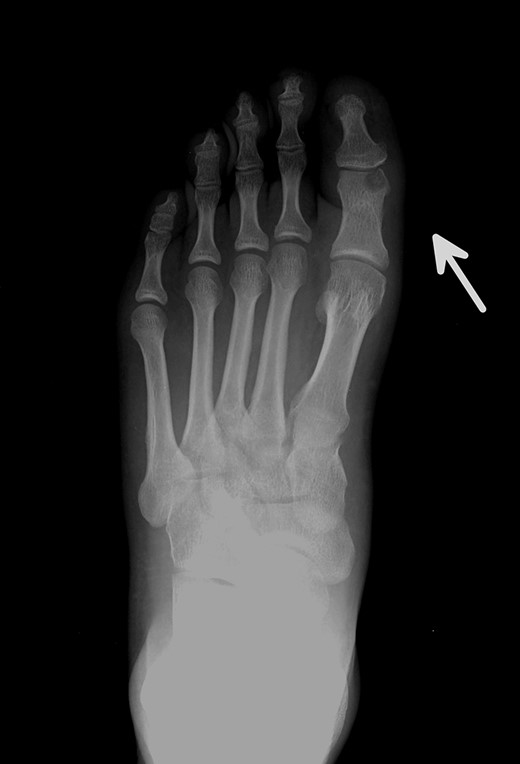

Posterior–anterior X-ray imaging of the left forefoot, showing an intra-articular osteolytic lesion (arrow) in the condyle of the proximal phalanx of the hallux.